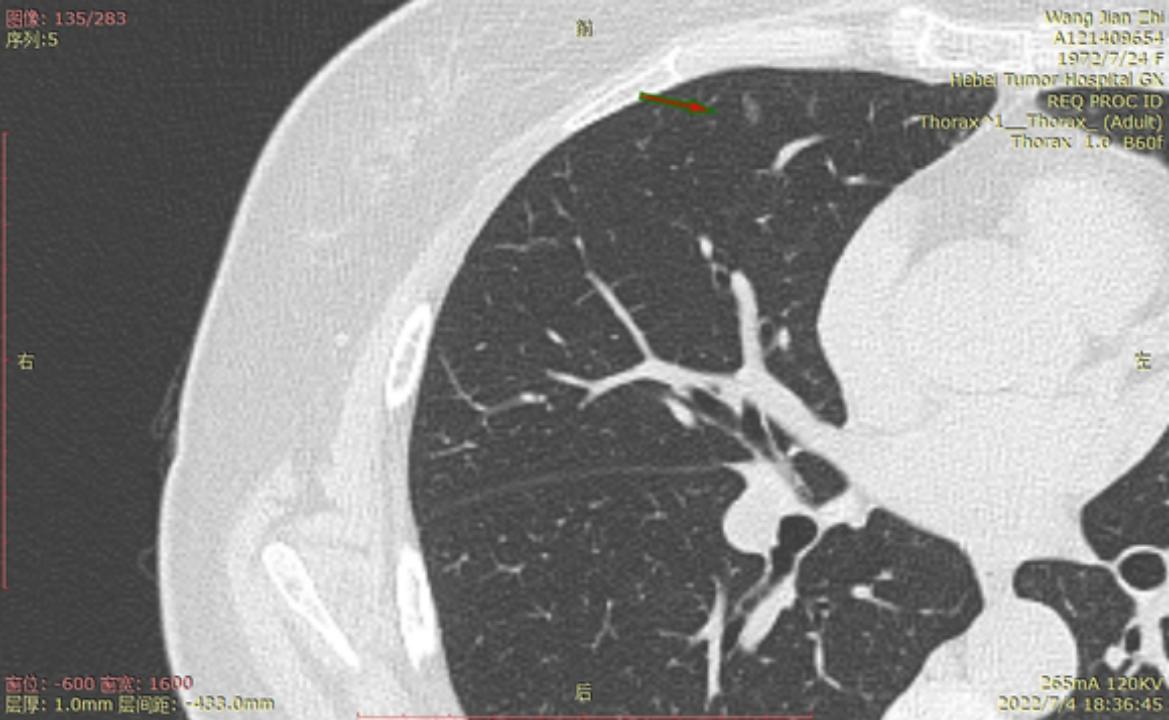

今年6月22号河北省人民医院进行CT检查后,报告双肺多发磨玻璃结节及微小结节以右肺为多,建议六个月后复诊。我于7月3号在河北省四院胸外科就诊,大夫建议复查薄层CT,7月4日CT结果报告示两肺多发结节,部分为磨玻璃密度,建议三个月复查,省四院的主任看了CT后有的建议立即住院手术,有的建议三个月复查,专家意见不一致,后来我看了主任的贴吧,首次发现肺结节先口服莫西沙星,三个月后再复查的贴吧,就没有立刻手术,从7月4日开始口服莫西沙星,现已完成15天疗程。等待复查的这一段时间里,总是担心大的结节已有浸润,请主任给予帮助,看看我的CT,给出我治疗建议,麻烦主任了!

结2